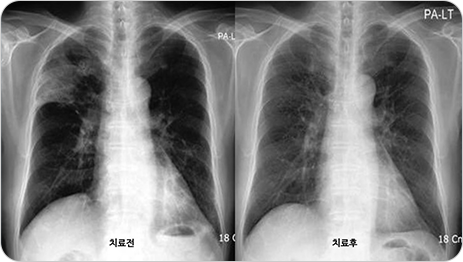

흉부 X선 촬영

침윤의 여부와 특징, 병변의 위치 및 침범 정도를 확인할 수 있습니다.

일부에서는 흉부 X선이 정상으로 보일 수도 있으며, 이 경우는 흉부전산화단층촬영(CT)으로 확인할 수 있습니다.

img